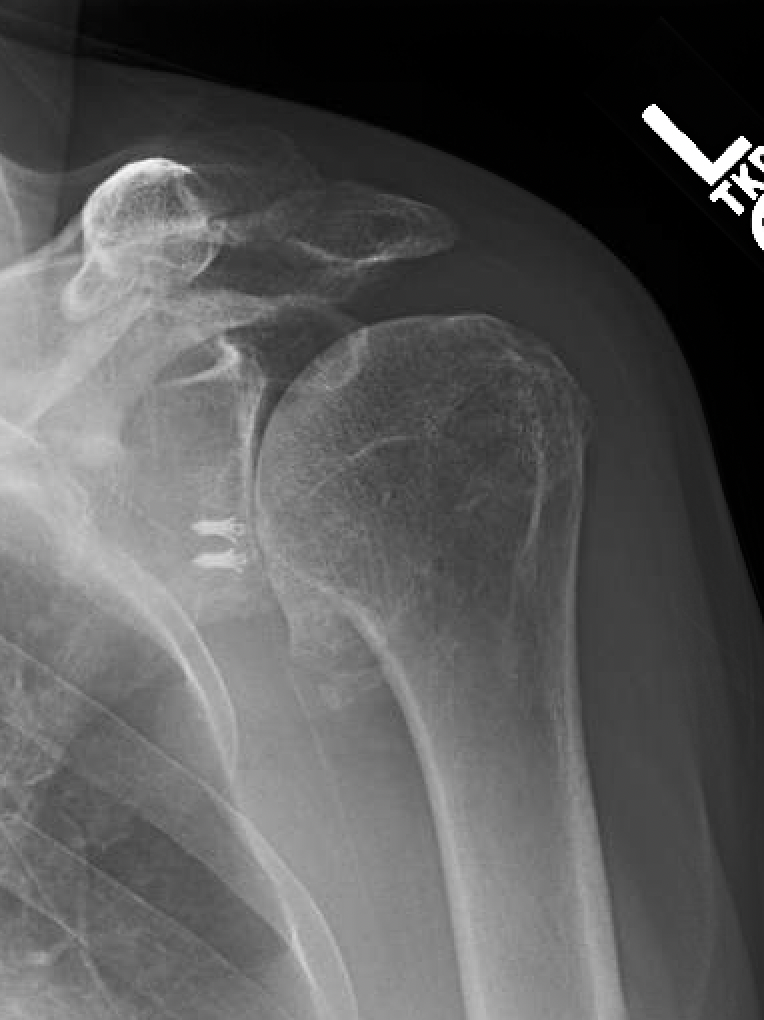

Shoulder Arthritis / Rotator Cuff Tears causes of shoulder pain Xrays for shoulder arthritis Can Arthritis Cause Rotator Cuff Tear this article discusses rotator cuff pain. rotator cuff tear arthropathy is a type of shoulder arthritis that can develop after a massive and prolonged rotator cuff tear. rotator cuff injuries are most often caused by progressive wear and tear of the tendon tissue over time. The torn rotator cuff can no longer hold the head of. It. Can Arthritis Cause Rotator Cuff Tear.

Shoulder Arthritis / Rotator Cuff Tears causes of shoulder pain Treating cuff tear arthropathy Can Arthritis Cause Rotator Cuff Tear rotator cuff injuries are most often caused by progressive wear and tear of the tendon tissue over time. rotator cuff tear arthropathy is a type of shoulder arthritis that can develop after a massive and prolonged rotator cuff tear. The four rotator cuff tendons in. An accident, such as a fall, can cause a broken collarbone or dislocated. Can Arthritis Cause Rotator Cuff Tear.

Shoulder Arthritis / Rotator Cuff Tears causes of shoulder pain Rotator cuff tear arthropathy Can Arthritis Cause Rotator Cuff Tear rotator cuff injuries are most often caused by progressive wear and tear of the tendon tissue over time. The torn rotator cuff can no longer hold the head of. An accident, such as a fall, can cause a broken collarbone or dislocated shoulder that tears your. what causes rotator cuff tears? rotator cuff tear arthropathy is a. Can Arthritis Cause Rotator Cuff Tear.

Rotator Cuff Tear Arthropathy Shoulder Arthritis shoulder surgeon in seattle Can Arthritis Cause Rotator Cuff Tear rotator cuff tear arthropathy is a type of shoulder arthritis that can develop after a massive and prolonged rotator cuff tear. An accident, such as a fall, can cause a broken collarbone or dislocated shoulder that tears your. The four rotator cuff tendons in. rotator cuff injuries are most often caused by progressive wear and tear of the. Can Arthritis Cause Rotator Cuff Tear.

Shoulder Arthritis / Rotator Cuff Tears causes of shoulder pain Rotator cuff tear arthropathy Can Arthritis Cause Rotator Cuff Tear An accident, such as a fall, can cause a broken collarbone or dislocated shoulder that tears your. rotator cuff tear arthropathy (or shoulder arthritis with a large rotator cuff tear) may result from rotator cuff tears. rotator cuff injuries are most often caused by progressive wear and tear of the tendon tissue over time. The four rotator cuff. Can Arthritis Cause Rotator Cuff Tear.